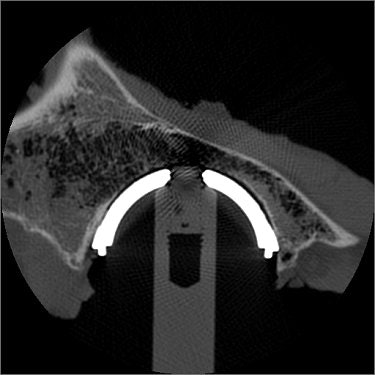

| CT image of an implanted dual-geometry acetabular cup. The majority of the bone-prosthesis contact occurs at the rim of the cup. Image courtesy of Dr. James Howard. |

"For each image, points were mapped on the inner bone surface and the outer prosthetic surface using customized software," the authors said. "The distance from each point on the prosthesis’ surface to the nearest point on the inner bone surface was measured." Contact was defined as bone-prosthesis distance of 0.5 mm or less.

The authors then used the CT images to create and analyze color maps. They found that with the Hemisphere, the contact pattern was relatively uniform across the cup surface. With the Interfit, CT revealed areas of bone-prosthesis distance near the dome of the cup, but a tighter rim fit. With the Trispike, there was less contact overall.